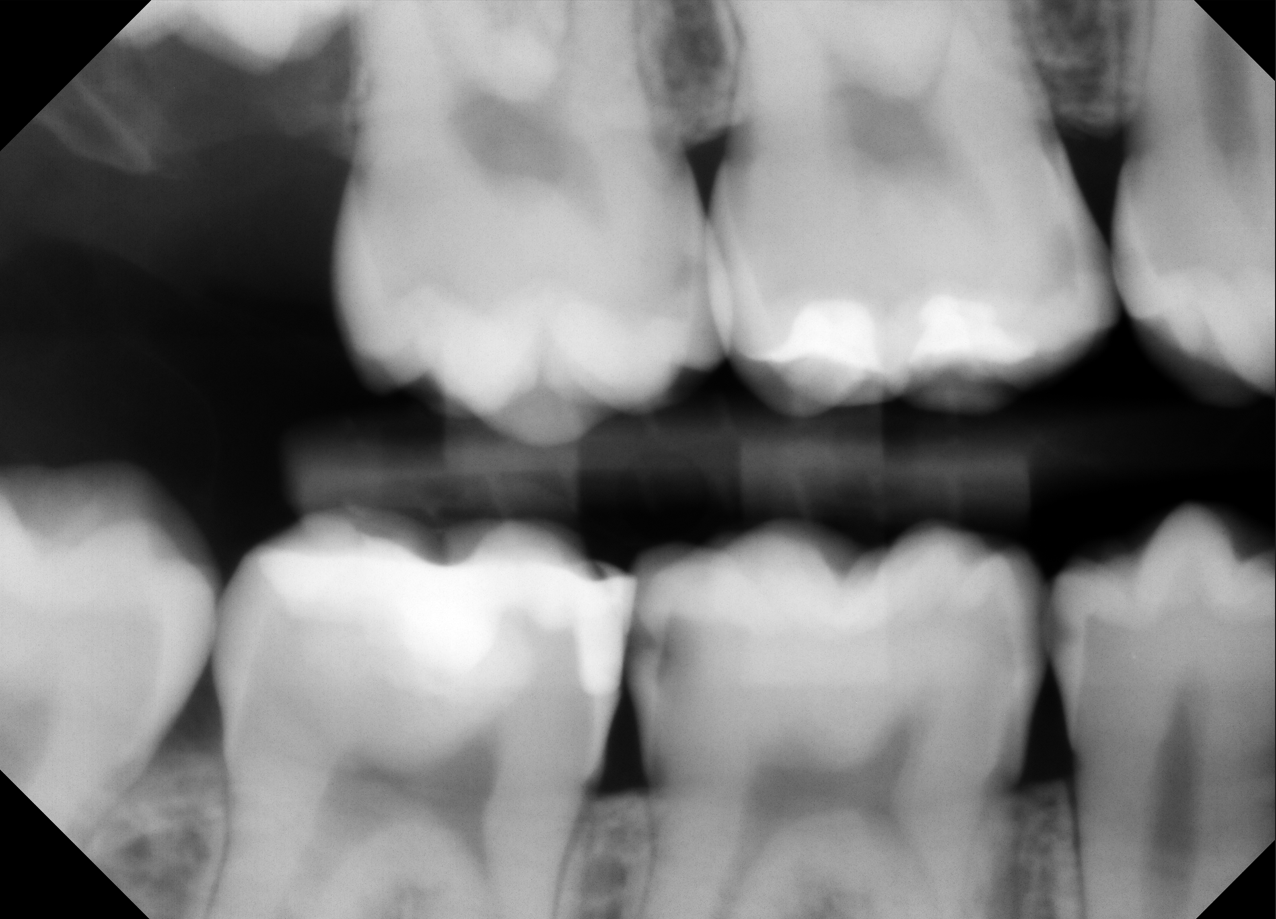

How Sugarbot Works

Simple. Visual. Immediate.

SugarBot is the ultimate lightweight dental imaging tool designed to support your diagnostics and improve patient understanding. No integration needed. Works with the dental software you already use.

1. Open Your Imaging Software.

Use your existing imaging software. No need to change a thing.

2. Click the X-Ray

One keystroke. That’s all it takes to launch the overlay.

3. Get Instant Clarity

Color-coded highlights show what may need a second look.

No new workflow. No new hardware. No learning curve.

Just better conversations